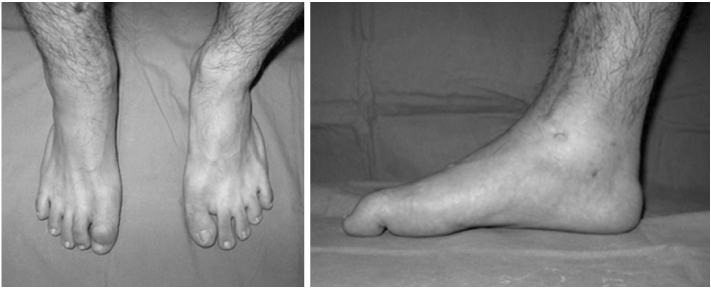

Fig. 1

Equinus of right ankle and flexion deformity of interphalangeal joint of great toe.

Fig. 1 Equinus of right ankle and flexion deformity of interphalangeal joint of great toe.